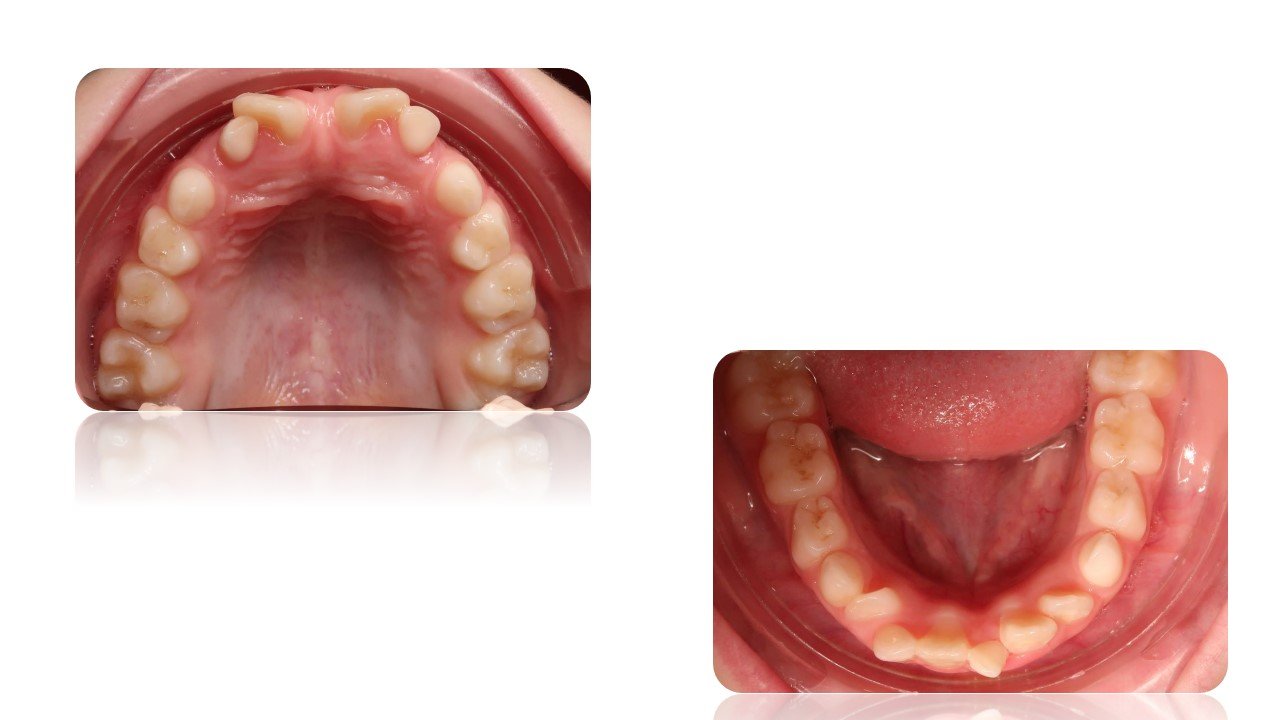

La Classe III Squelettiques

Les classes III squelettiques sont l’expression d’une orientation pathologique du plan occlusal et de la croissance faciale.

L’orthodontie systémique permet d’appréhender cette pathologie par l’analyse des latéralités mandibulaires.

Le traitement qui en découle est donc fonctionnel et stable car il permet non pas seulement une protraction du maxillaire mais une réorientation complète de celui-ci. Cette prise en charge permet de retrouver une proprioception maximale du prémaxillaire dans la mastication, gage de stabilité à long terme.